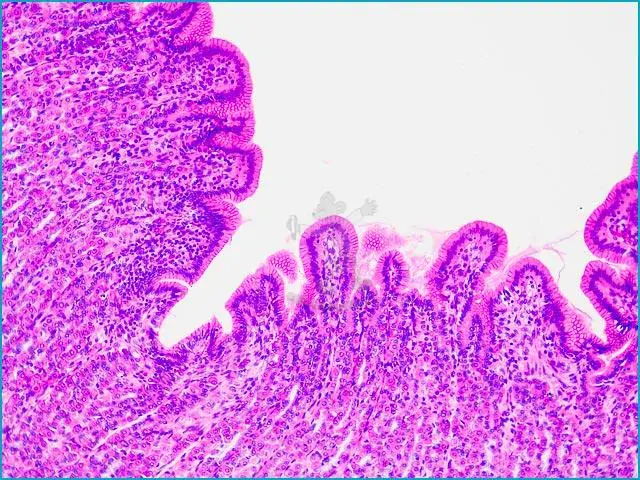

Mikroskopické preparáty – školní sada pro histologii č. 1, 23 ks